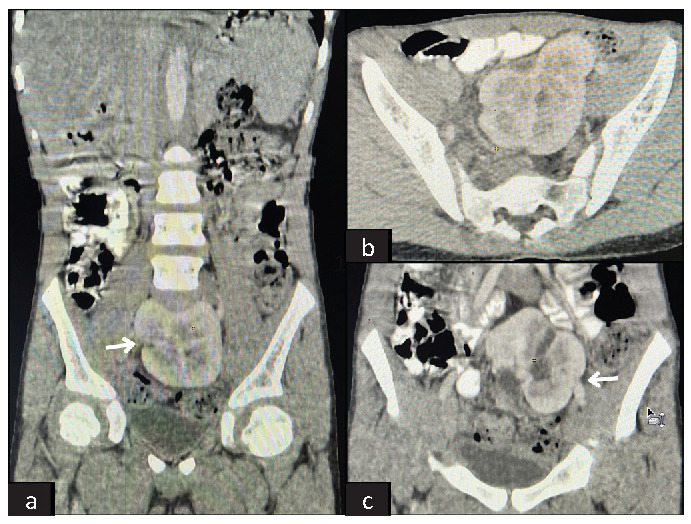

Pancake Kidney: A Rare Case of Renal Ectopia.

煎饼肾:一例罕见的肾异位。